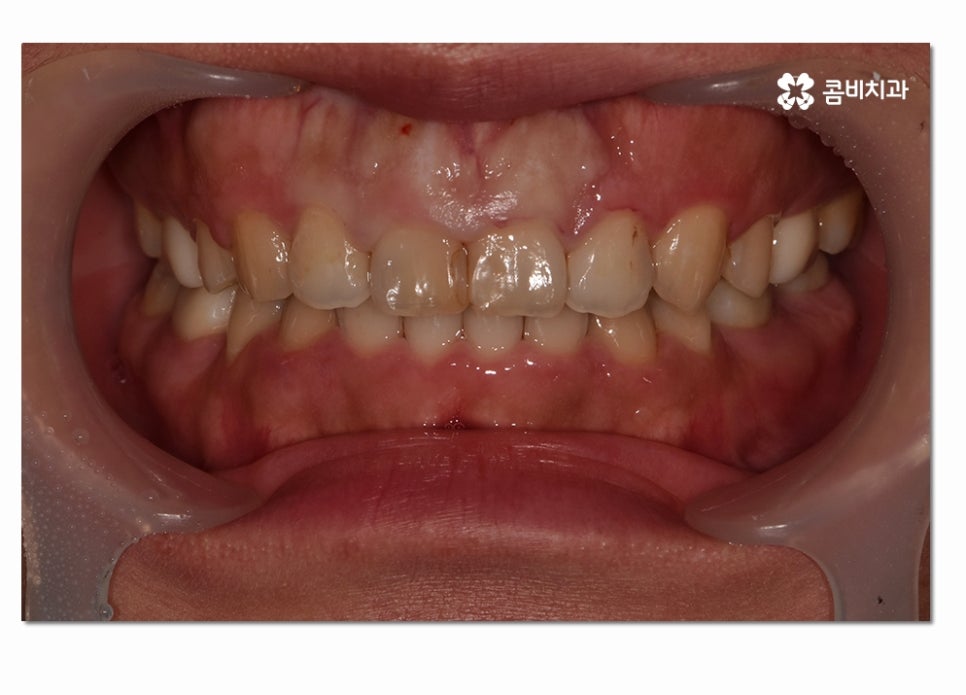

일반적으로 치아를 상실하게 되는 원인에 대해서 충치를 먼저 떠올리시는 분들이

많은데 치아를 잃게 되는 요인으로는 충치나 사고가 원인이 되는 경우도

많겠지만 나이가 들수록 치주 질환으로 인해 치아손상을 유발하는 경우를 많이 볼 수 있어요.

잇몸 병으로도 불리는 치주 질환은 초기에 제대로 된 치료를 하지 않을 경우

치은부터 치조골, 치주 인대 등을 순차적으로 파괴시키면서 결국

치아가 흔들리게 되고 발치로 이어질 수 있기 때문에

치은염이 치주염으로 더 커지지 않도록 주의해야 할 필요가 있는데요.

치주 질환은 진행 단계에 따라서 치은에 국한되어 염증이 발생하는

치은염과 이 시기에 제대로 된 치료를 받지 않고

염증이 치조골까지 이르게 되었을 때를 일컫는 치주염으로 나눌 수 있는데요.